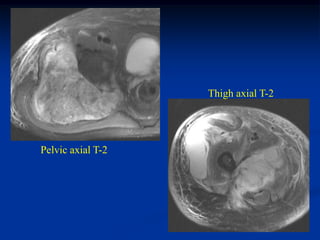

Case #250.3      Sag T-2                 Sag Gad

15 year female with painful enlarging desmoid past 6 months

while on chemotherapy

Axial T-2

vessels

Axial Gad